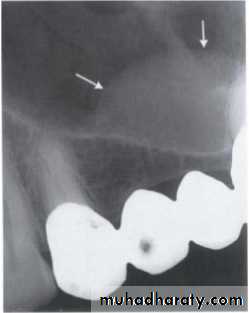

Benign cyst: lack of peripheral cortex(retention

pseudo cyst) indicates that it originated in the

sinus (non-odontogenic origin).

principles of radiographic interpretation